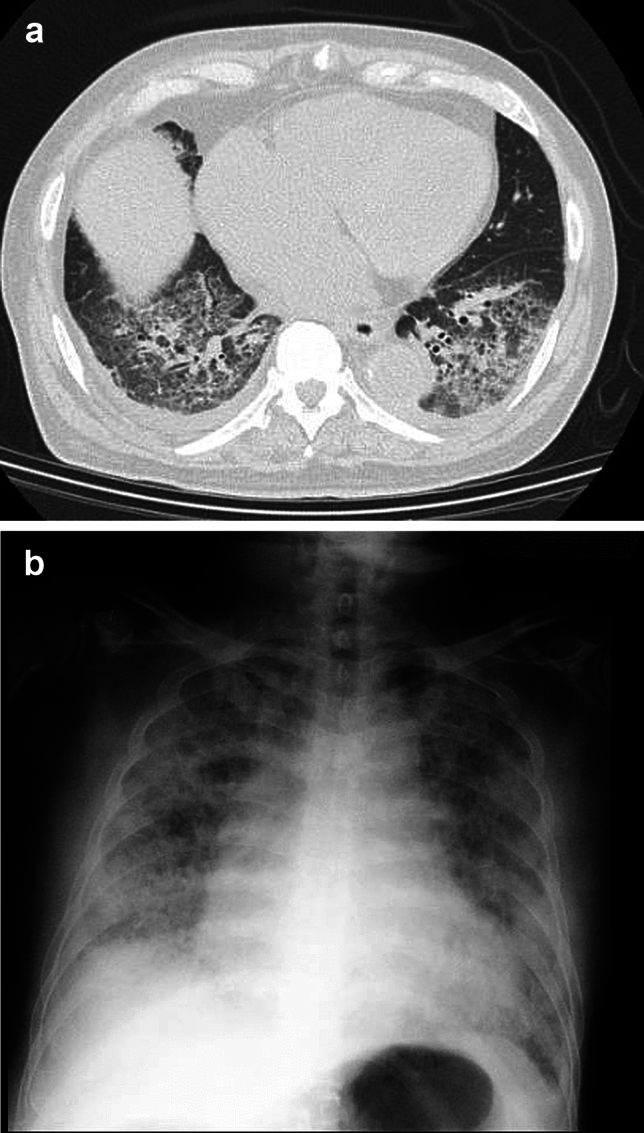

结直肠癌仍然是世界范围内死亡的主要原因,早期发现对于改善预后至关重要。CT结肠镜检查(CTC)已成为一种有前途的替代光学结肠镜检查大肠癌筛查。本文探讨了CTC在日本的发展潜力,重点关注质量控制、患者可接受性、并发症及其在筛查项目中的作用。CTC检测结直肠息肉具有较高的敏感性和特异性,对≥10 mm病变的诊断效果与结肠镜相当。粪便标记和双位置成像等技术可显著提高诊断准确性。然而,诊断结果的可变性强调了严格的解释培训和质量控制的必要性。美国放射学会建议至少对50例结肠镜检查证实的病例进行培训。尽管CTC有诸多优势,但由于医疗专业人员的认知度低、训练有素的放射科医生短缺以及缺乏支持使用CTC的具体指导方针,日本采用CTC的程度仍然有限。与结肠镜检查相比,CTC的非侵入性、更短的检查时间和更少的肠道准备要求,使患者对CTC的接受度很高。然而,并发症,如肠穿孔,虽然罕见,需要仔细的风险评估。虽然CTC在美国和欧洲已被认可用于筛查和诊断随访,但将其纳入日本的结直肠癌筛查指南对于扩大其应用至关重要。为了最大限度地发挥反恐的效益,必须努力使方法标准化,建立质量指标,并就降低死亡率和成本效益产生强有力的证据。

Colorectal cancer remains a leading cause of mortality worldwide, and early detection is essential for improving outcomes. CT colonography (CTC) has emerged as a promising alternative to optical colonoscopy for colorectal cancer screening. This article explores the potential of CTC in Japan, focusing on quality control, patient acceptability, complications, and its role in screening programs. CTC has demonstrated high sensitivity and specificity for detecting colorectal polyps, with its diagnostic performance comparable to colonoscopy for lesions ≥ 10 mm. Techniques such as fecal tagging and dual-position imaging significantly enhance diagnostic accuracy. However, the variability in diagnostic outcomes underscores the need for rigorous interpretation training and quality control. The American College of Radiology recommends training with at least 50 cases verified by colonoscopy. Despite its advantages, the adoption of CTC in Japan remains limited due to low awareness among medical professionals, a shortage of trained radiologists, and the absence of specific guidelines endorsing its use. Patient acceptability for CTC is high due to its non-invasive nature, shorter examination time, and reduced bowel preparation requirements compared to colonoscopy. Nonetheless, complications such as bowel perforation, albeit rare, necessitate careful risk assessment. While CTC has been recognized in the U.S. and Europe for screening and diagnostic follow-up, its integration into Japan's colorectal cancer screening guidelines is crucial to expand its utilization. To maximize the benefits of CTC, efforts must focus on standardizing methodologies, establishing quality indicators, and generating robust evidence on mortality reduction and cost-effectiveness.